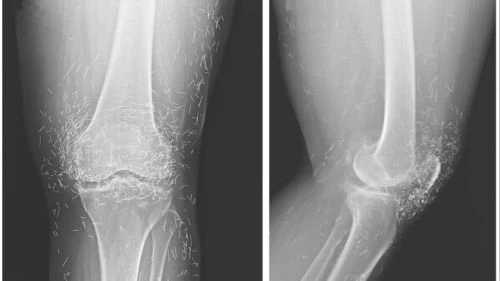

Hàng trăm kim châm cứu bằng vàng trong đầu gối

Kiểm tra hình ảnh X-quang đầu gối của một phụ nữ 65 tuổi ở Hàn Quốc, bác sĩ phát hiện hàng trăm chiếc kim châm cứu bằng vàng nhỏ li ti trong mô.

Ảnh. Hình ảnh X-quang cho thấy hàng trăm mũi kim bằng vàng được cho là để lại có chủ đích nhằm mục đích kích thích giảm đau. (livescience.com)

Hình ảnh X-quang cho thấy hàng trăm mũi kim bằng vàng được cho là để lại có chủ đích nhằm kích thích giảm đau. Ảnh: livescience.com.

Trong bài viết của các bác sĩ công bố trên New England Journal of Medicine, với trường hợp của bà, mũi kim được cho là làm bằng vàng, vẫn ở lại trong mô một cách có chủ ý nhằm tiếp tục kích thích giảm đau. Tuy nhiên, việc để lại kim châm hay bất cứ vật thể nào trong cơ thể hoàn toàn không phải là ý tưởng hay, theo nhận định của tiến sĩ Ali Guermazi, giáo sư X-quang học tại ĐH Boston (Mỹ). Theo ông, vật lạ xâm nhập vào cơ thể có thể gây viêm, áp xe và nhiễm trùng. Nó cũng gây khó khăn cho việc đọc phim X-quang của các bác sĩ.